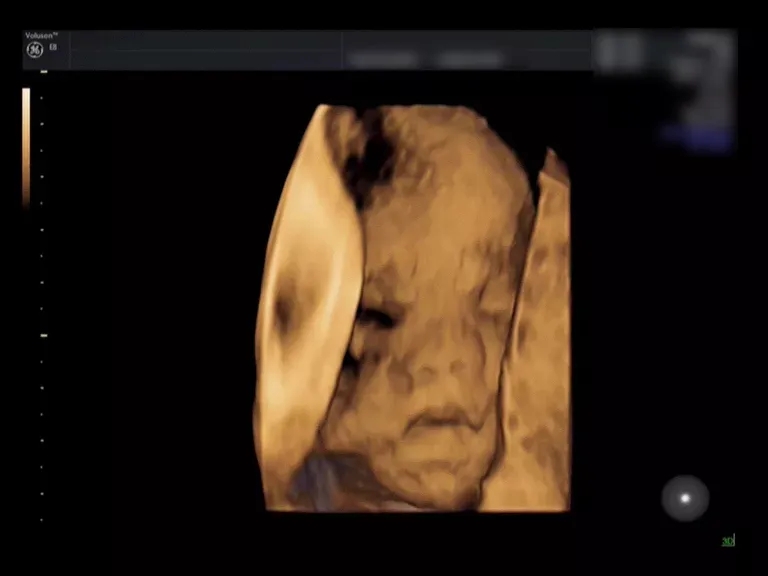

来看这个小baby的彩超对比

就一目了然啦

(三维超声)